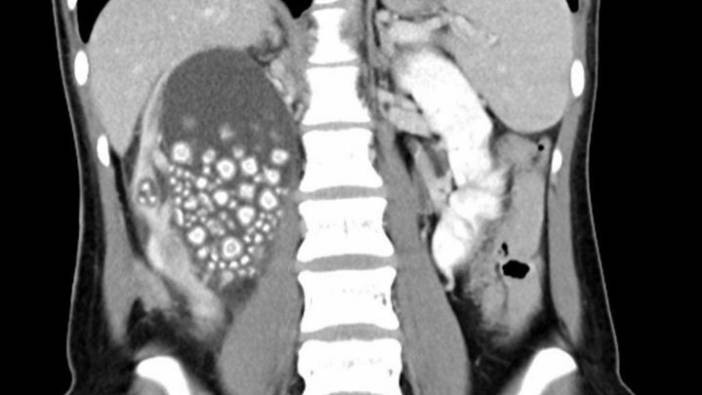

Son yıllarda kronik böbrek yetmezliğinin dünya genelinde salgın benzeri bir artış gösterdiğini belirten Dr. Özlem Yayar, bu durumun ciddi bir sağlık sorunu olduğunu ifade etti. Şeker hastalığı, yüksek tansiyon, nefritler, kistik böbrek hastalıkları ve ürolojik problemlerin kronik böbrek hastalığının en yaygın nedenleri olduğunu söyledi. Özellikle şeker hastalığı, hipertansiyon, kalp hastalığı, şişmanlık, ileri yaş, ailede böbrek hastalığı öyküsü, sigara ve sık ağrı kesici ilaç kullanımının kişiyi böbrek hastalığı açısından yüksek risk altına soktuğunu belirtti.